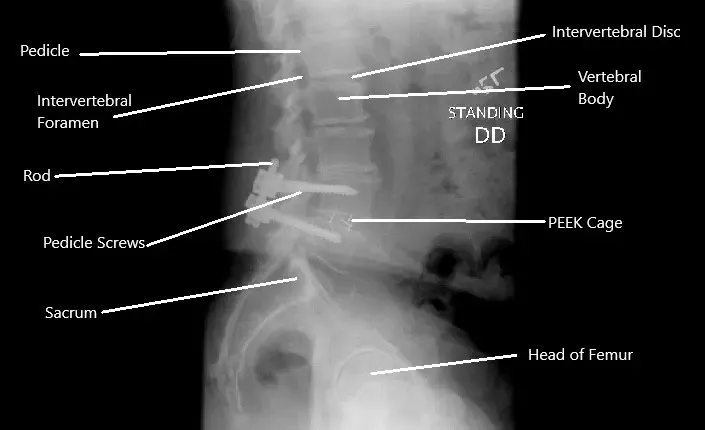

Radiografía que muestra descompresión y fusión de las vértebras L4-L5.

Las opciones quirúrgicas más comunes incluyen:

- Reparación de Pars: Corrige pequeñas fracturas en el pars interarticular.

- Descompresión (laminectomía): Elimina el tejido que presiona los nervios.

- Fusión espinal: Estabiliza las vértebras afectadas mediante tornillos, varillas o injertos óseos.